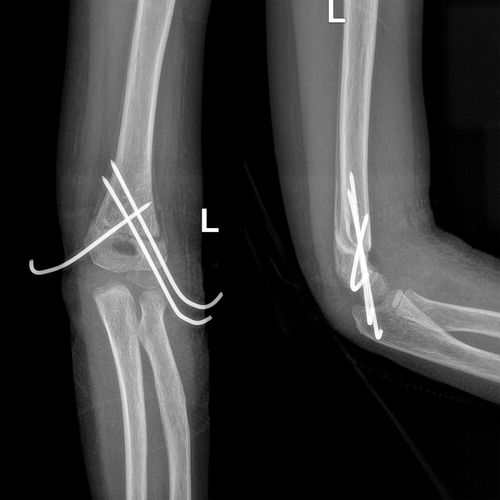

(3)营养不良型骨不连 骨折端无肥大及骨痂,常常因骨折对位不良引起